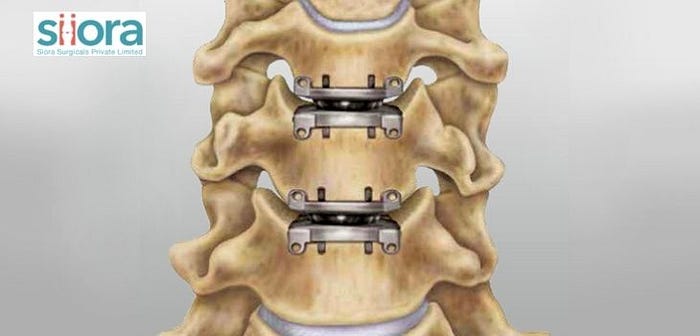

Degeneration or herniation of vertebral disc(s) reduces the space for the nerve roots to function properly, and due to this, certain complications may be experienced by the person. The complications seen may include chronic pain, weakness starting from the neck to the arm, numbness, and tingling. Thus, cervical disc arthroplasty will aim to remove the damaged disc and fix an artificial one at its place.